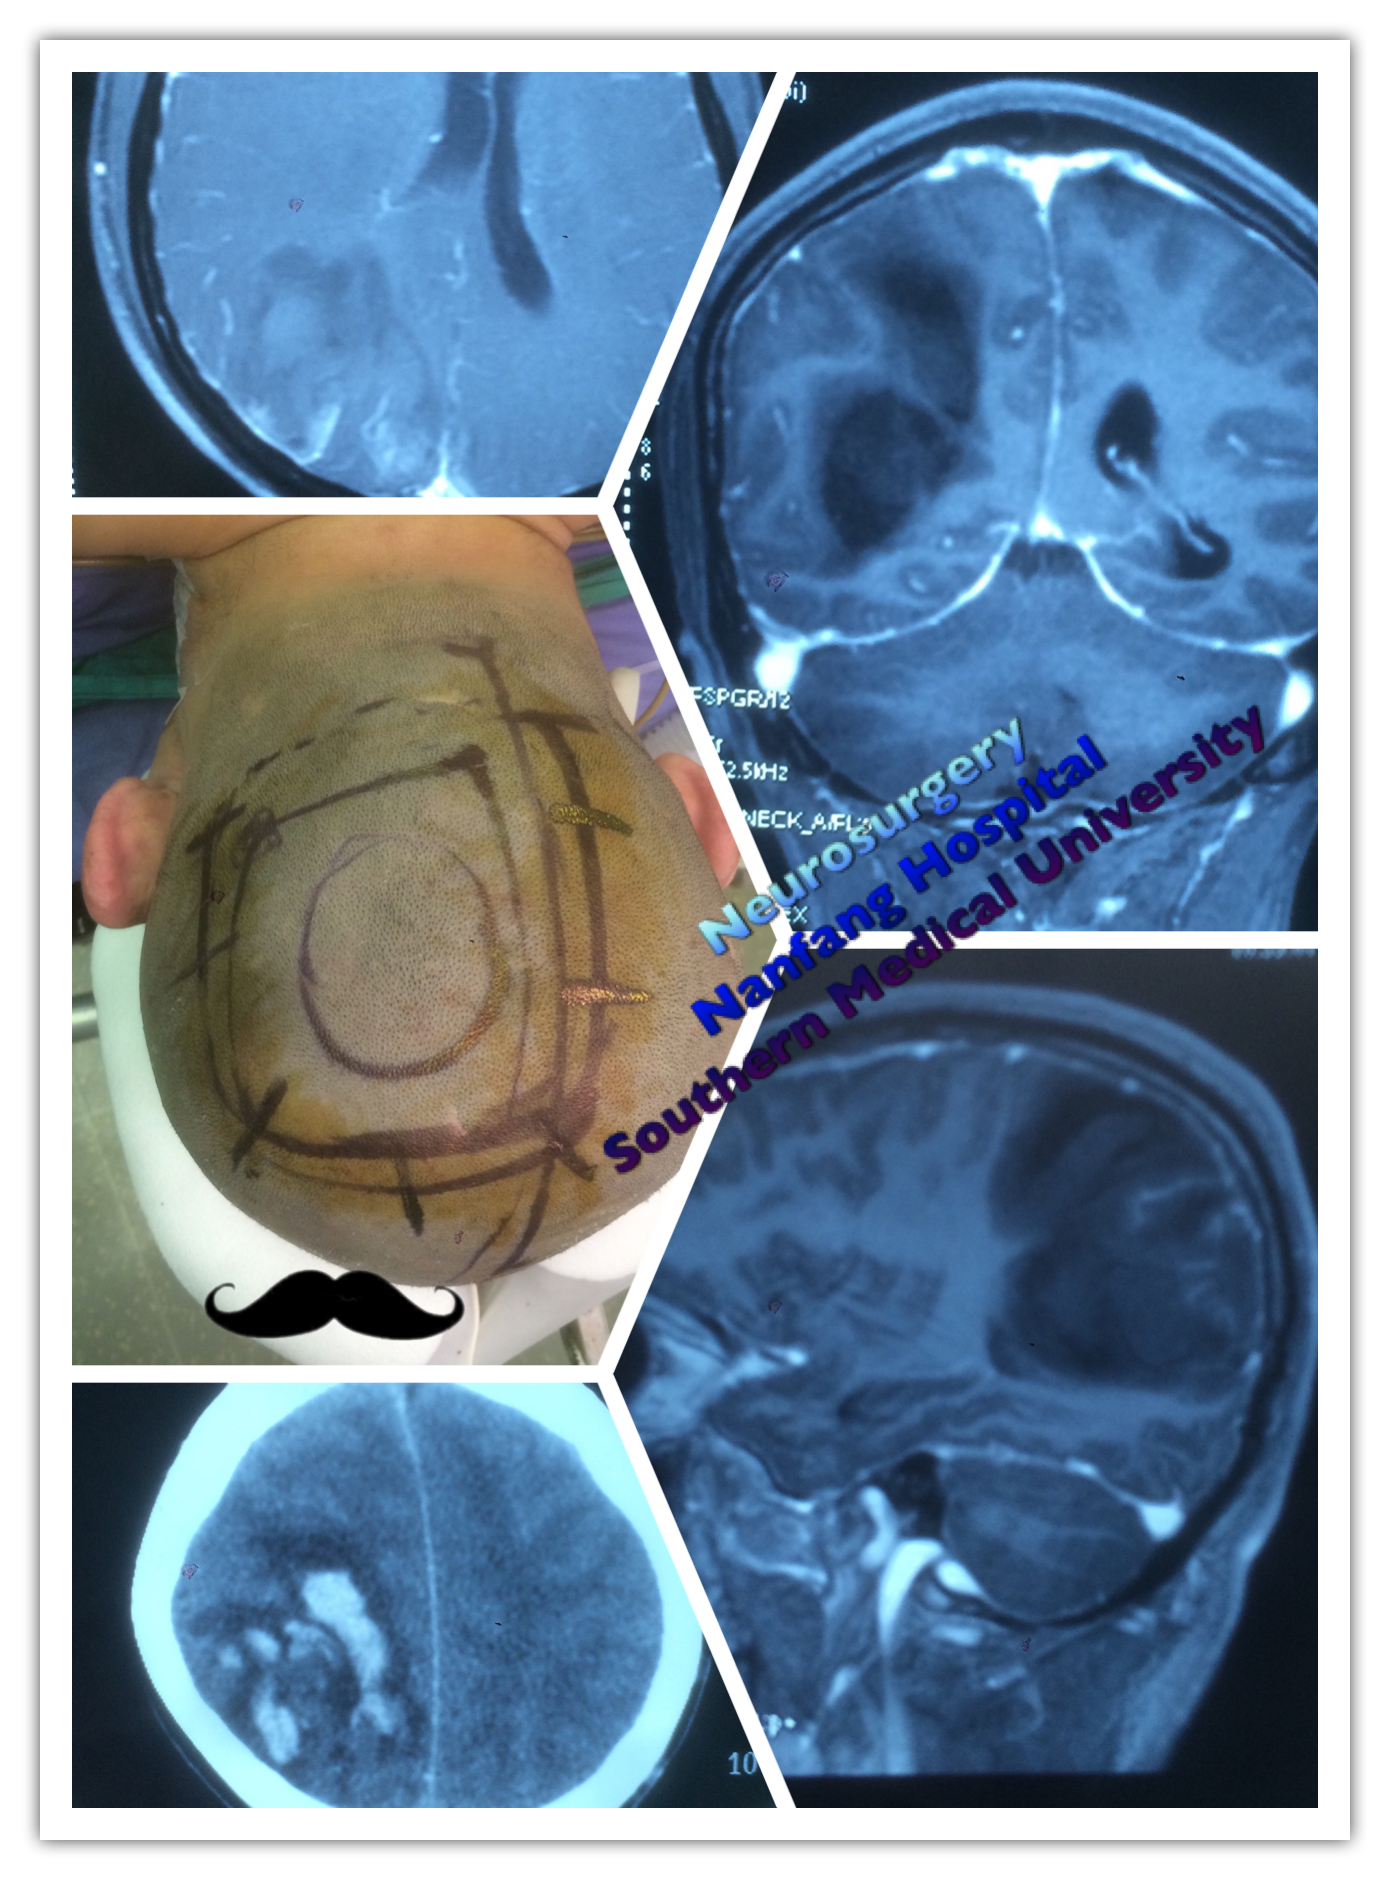

患者于2019-8-29在全麻下行右侧翼点入路右侧脑室前角占位切除术.